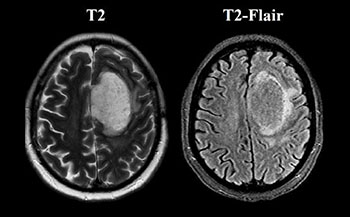

МРТ головного мозга и DSC-перфузия. Крупное интрааксиальное образование локализованное  в верхней лобной извилине левого полушария, окруженное перифокальным отеком ( с наличием феномена несоответствия Т2-Т2flair (mismatch sign)), с частичным вовлечением тела мозолистого тела. Видимого ограничения диффузии не отмечается, однако есть некая неоднородность в структуре опухоли, отчетливо визуализируется сеть патологически расширенных сосудов на ИП SWAN, а так же узловое накопление парамагнетика образованием на постконтрастных Т1-ВИ с отчетливо повышенными значениями rCBV в 5-7 раз по периферии.

N.B. Феномен несоответствия Т2-Т2flair (T2-Flair mismatch sign) – проявление, которое считается высокоспецифичным для диффузных глиом и анапластических астроцитом у взрослой популяции, указывающее на мутантный статус опухоли без ко-делеции 1p\19q, что в свою  очередь может помочь в определении тактики лечения и предположения прогноза у пациента (неинвазивный биомаркер определения IDH статуса)